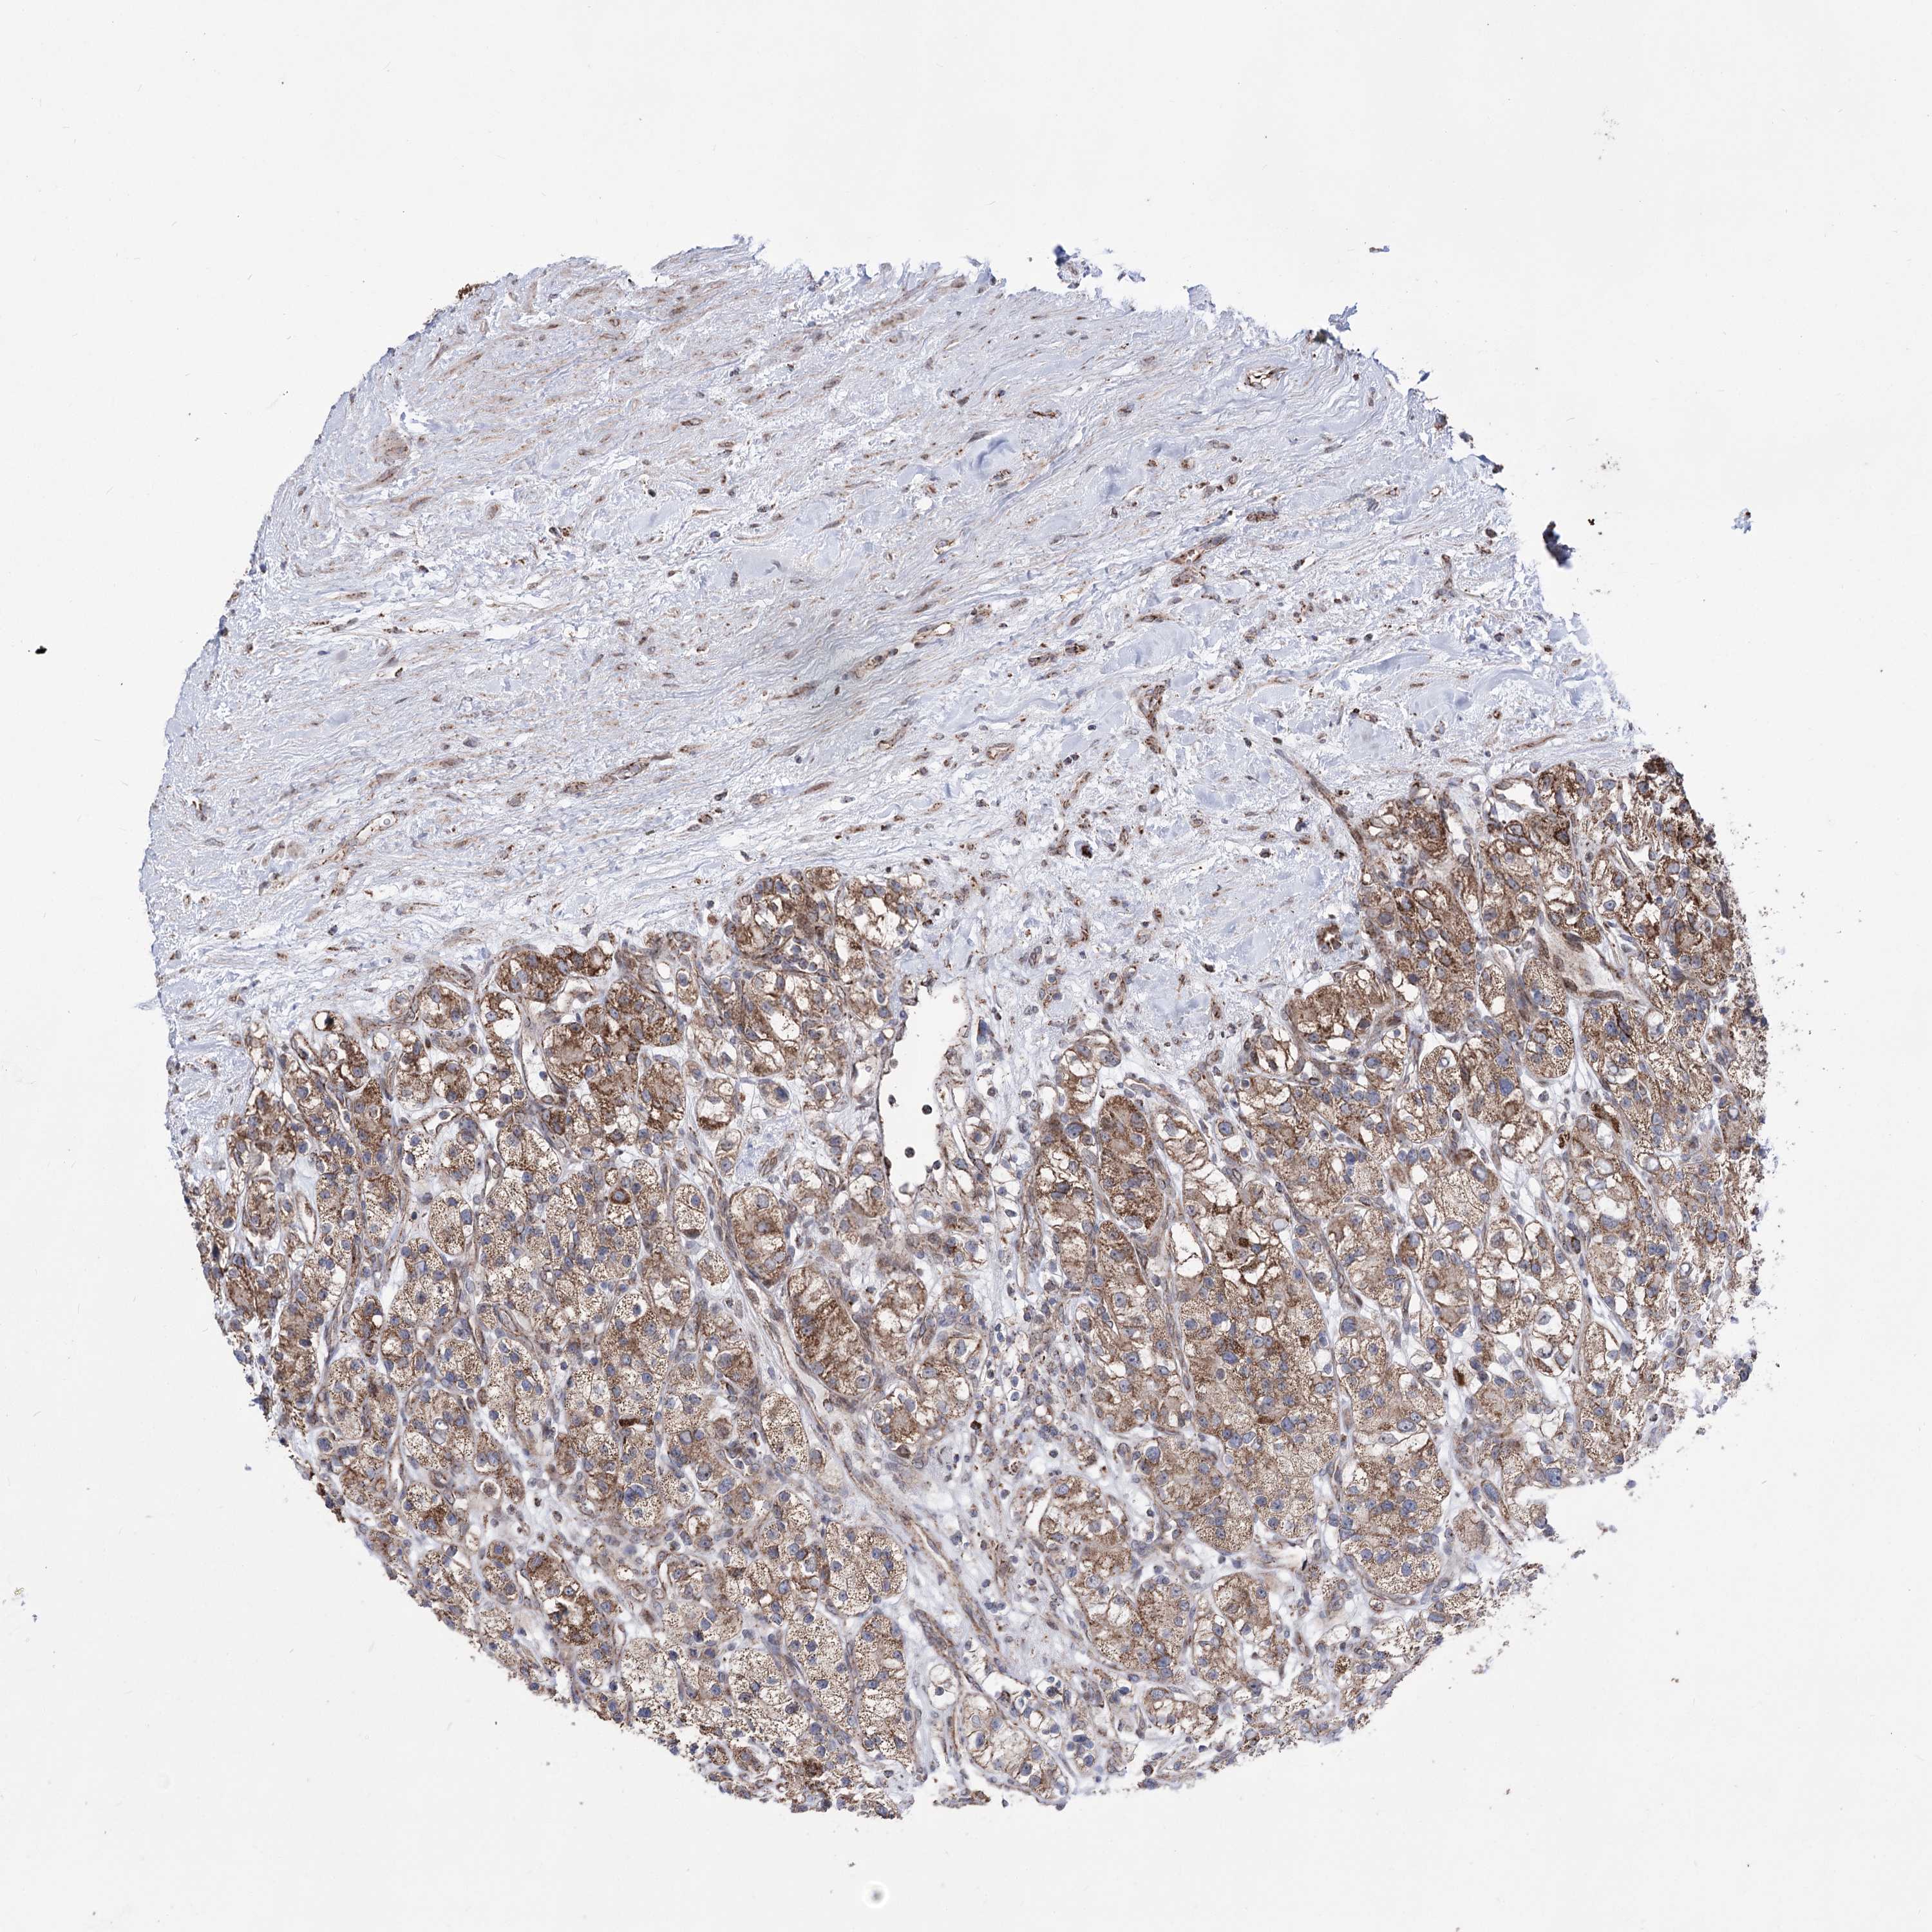

KIDNEY RENAL CLEAR CELL CARCINOMA (VALIDATION) - Interactive survival scatter ploti

The Survival Scatter plot shows the clinical status (i.e. dead or alive) for all individuals in the patient cohort, based on the same data that underlies the corresponding Kaplan-Meier plots. Patients that are alive at last time for follow-up are shown in blue and patients who have died during the study are shown in red.

The x-axis shows the expression levels (FPKM) of the investigated gene in the tumor tissue at the time of diagnosis. The y-axis shows the follow-up time after diagnosis (years). Both axes are complimented with kernel density curves demonstrating the data density over the axes. The top density plot shows the expression levels (FPKM) distribution among dead (red) and alive patients (blue). The right density plot shows the data density of the survived years of dead patients with high and low expression levels respectively, stratified using the cutoff indicated by the vertical dashed line through the Survival Scatter plot. This cutoff is automatically defined based on the FPKM cutoff that minimizes the p-score. The cutoff can be changed by dragging the vertical line or by entering a cutoff value in the square labeled "Current cut-off".

Under the Survival Scatter plot the p-score landscape (black curve; left axis) is shown together with dead median separation (red curve; right axis). Dead median separation is the difference in median mRNA expression between patients who have died with high and low expression, respectively. It is calculated as follows: median FPKM expression of dead patients with high expression - median FPKM expression of dead patients with low expression. This is intended to aid the user in visually exploring custom cutoffs and the associated p-scores and dead median separation.

Individual patient data is displayed and can be filtered by clicking on one or more of the category buttons on the top of the page. Categories describing expression level and patient information include: high, low, alive, dead, female, male and tumor stages. The scale of the x-axis can be toggled between linear and log-scale by clicking on the "x log" button. Mouse-over function shows TCGA ID, patient information and mRNA expression (FPKM) for each patient.

& Survival analysisi

Kaplan-Meier plots summarize results from analysis of correlation between mRNA expression level and patient survival. Patients were divided based on level of expression into one of the two groups "low" (under cut off) or "high" (over cut off). X-axis shows time for survival (years) and y-axis shows the probability of survival, where 1.0 corresponds to 100 percent.

CREB3L4 is not prognostic in Kidney Renal Clear Cell Carcinoma (validation)

Best expression cut offi

Based on the FPKM value of each gene, patients were classified into two groups and association between prognosis (survival) and gene expression (FPKM) was examined. The best expression cut-off refers the FPKM value that yields maximal difference with regard to survival between the two groups at the lowest log-rank P-value. Best expression cut-off was selected based on survival analysis .

When clicking on this number, the vertical dashed line indicating cut-off, the interactive survival plot, and the Kaplan-Meier curve will be adjusted to show results based on the best expression cut-off.

: 11.58

TCGA RNA samplesi

RNA-seq data is reported as average FPKM (number Fragments Per Kilobase of exon per Million reads), generated by the The Cancer Genome Atlas (TCGA) .

Normal distribution across the dataset is visualized with box plots, shown as median and 25th and 75th percentiles. Points are displayed as outliers if they are above or below 1.5 times the interquartile range. FPKM values of the individual samples are presented next to the box plot.

Average pTPM 14.7

Number of samples 100